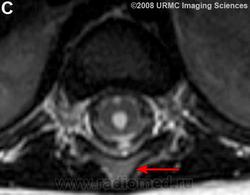

Желудочек терминальный (ventriculus terminalis, PNA, BNA, JNA; син. Краузе желудочек) — расширение в концевом отрезке центрального канала спинного мозга, расположенное в мозговом конусе вблизи от задней его стенки.

Желудочек терминальный

МРТ.  Терминальный желудочек

http://www.radsource.us/clinic/0807